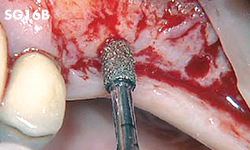

Unilateral anterior mandibular sampling

Excision of bone torus

Anterior mandibylar harvesting

Mandibular harvesting at approach stage

The cutting part is bone torus